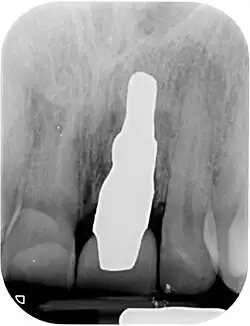

A root-analogue dental implant (RAI) – also known as a truly anatomic dental implant, or an anatomical/custom implant – is a medical device to replace one or more roots of a single tooth immediately after extraction.[1] In contrast to common titanium screw type implants, these implants are custom-made to exactly match the extraction socket of the specific patient. Thus there is usually no need for surgery.[2]

As the root analogue dental implant matches the dental alveolus (tooth socket) it can only be placed immediately after the tooth extraction. If the tooth has been already lost and the soft and hard tissue is already healed, an RAI can no longer be placed.[1]

RAIs are custom made to perfectly fit the tooth socket of a specific patient immediately after tooth extraction. Therefore every implant is unique. As an optimised root-form it is much more than a simple 1:1 replica of a tooth. Since it exactly fills the gap left after the tooth is extracted, surgery is rarely needed. The implant can be produced from a copy of the extracted tooth, an impression of the tooth socket, or from a CT scan or CBCT scan.[7] The advantage of a CBCT scan is that the implant can be produced before extraction. With the former methods, it takes one or two days to fabricate an implant.

A root analogue implant can be fabricated from zirconium dioxide (zirconia) or titanium.[8] Successful titanium RAIs have been three-dimensionally printed as porous one-piece implants, using CAD software.[9] However, zirconia is the preferred material, because it is more esthetic in colour, with no grey discolouration visible through gums.[10][5]